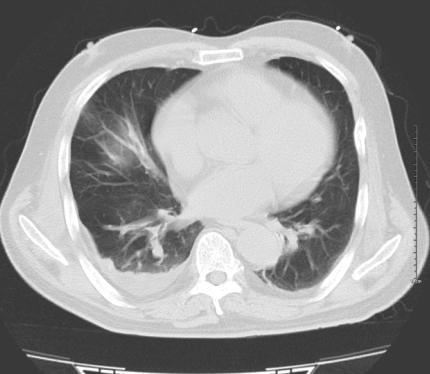

肺窗示:双侧胸廓对称,两肺野内未见明显异常密度影。右下肺见片状渗出灶,所示气管支气管开口通气良好。

纵隔窗示:左心室增大,各大血管走行自然,未见明显扩张征象。两肺门区及纵隔内未见异常肿大的淋巴结。右侧胸腔积液。